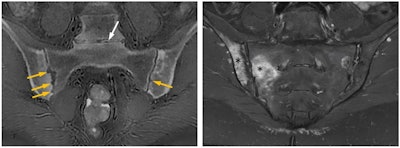

"ZTE may remove the need for CT, with detailed depiction of bone anatomy, making an MRI examination a one-stop imaging examination for conditions such as femoroacetabular impingement, giving both soft tissue and bone imaging within the same examination," she noted. "Substantial agreement is being found in morphometric analyses, with reproducibility of many lytic or sclerotic lesions -- although spatial resolution is still inferior to CT or radiography."

It has shown value in bone morphology, assessment of fractures, displaced bone fragments, shoulder instability, calcification (ossification of ligaments, calcific tendinitis) spinal foramina stenosis, skull assessment (suture closure, trauma), and assessment of bone erosions in bone tumors, Prince added. It may also demonstrate a wide range of structural abnormalities and disease or healing processes.